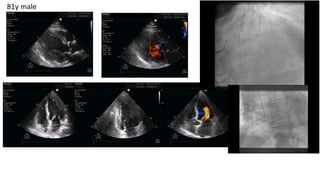

81y male

• Take into account the effects of arterial blood

pressure (afterload), inotropes, and vasopressors.

• Heart rate or AF could difficult interpretation, risk of

underestimation

• Beware of normal or high LVEF may misled maybe a

marked diastolic or valvular dysfunction is present.

• TDI: S’ >7.5 correlated with an LVEF >50 %, but

S´decreases with age

Left ventricular systolic function

McLean AS. Critical Care 2016;20:275